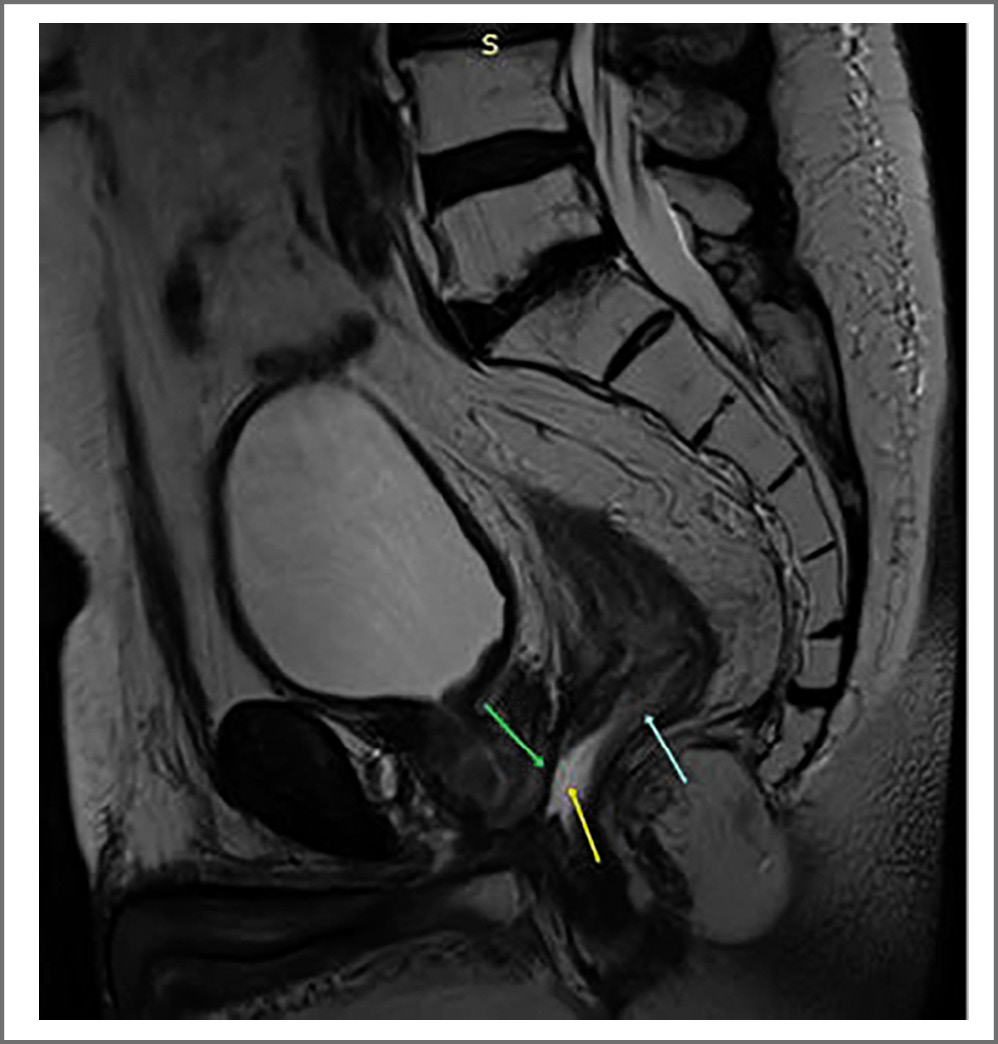

С февраля по декабрь 2021 г. отмечали рост ПСА с 0,27 до 10,05 нг/мл, в связи с чем пациенту выполнили МРТ органов малого таза, в результате убедительных данных за наличие зон с высокой целлюлярностью в зоне сканирования не получили. На рис. 2 (Т2-взвешенное изображение) зеленой стрелкой показано истончение (дефект) передней стенки прямой кишки, голубой – некоторое повышение сигнала от стенки и утолщение, возможно воспалительные изменения, желтой – пристеночное жидкостное содержимое. Пациенту назначили гормональную терапию (Золадекс 10,8 мг). Для уточнения признаков метастазирования рака простаты и необходимости ЛТ пациенту сделали позитронно-эмиссионную томографию, совмещенную с компьютерной томографией, по результатам которой на серии томограмм костной системы отмечается ПСМА-позитивный бластический метастаз в TIX [очаг размером 37×37 мм с SUV (Standardized Uptake Value – стандартизированный уровень захвата) 26 г/мл с накоплением радиофармпрепарата]; рис. 3. С учетом выявленного поражения позвоночника пациенту провели локальное стереотаксическое облучение TIX в режиме 3 фракций по 10 Гр, эквивалентная СОД 98,4 Гр, с положительным эффектом. Контрольный уровень ПСА стал в референсных значениях.

Рис. 2. МРТ органов малого таза от 27 января 2022 г. Т2-взвешенное изображение. Истончение (дефект), воспалительные изменения передней стенки прямой кишки и жидкостное содержимое.

Fig. 2. Magnetic resonance imaging of the pelvic organs, January 27, 2022. T2 VI. Thinning (defect), inflammatory changes in the anterior wall of the rectum and fluid contents.